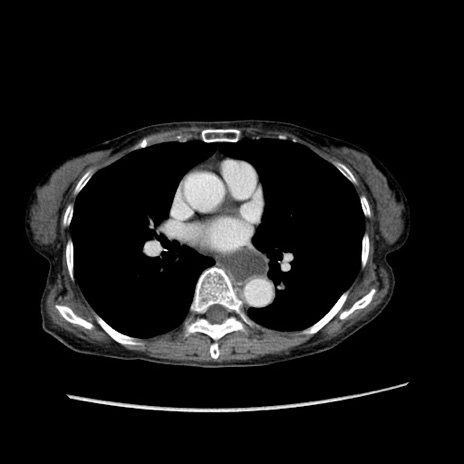

症例25(横断像)

【症例】80歳代女性

【主訴】胸のつかえ感

【現病歴】約9時間前に食後から胸のつかえた感じあり、嘔吐あり、来院。

【既往歴】胃癌(全摘)、胆摘、虫垂炎

【身体所見】心窩部に圧痛あり、反跳痛なし。

【データ】WBC 5700、CRP 0.05